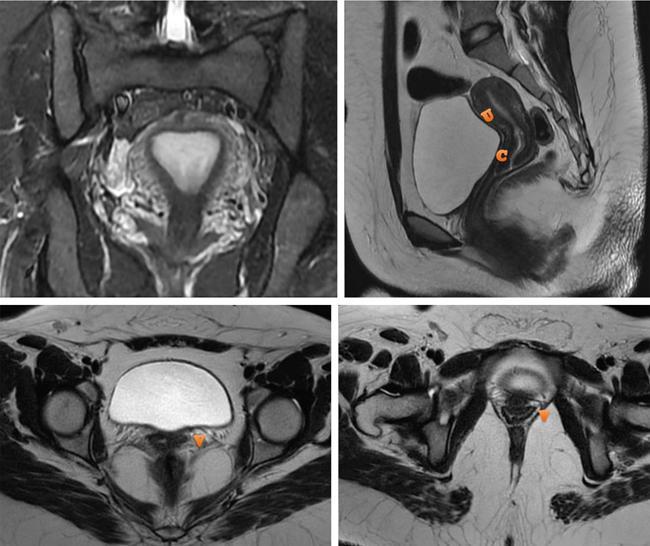

MÜLLERIAN DUCT ANOMALIES Rajani Gorantla Müllerian ducts are a pair of tubular structures that give rise to uterus, cervix, fallopian tubes and upper two-thirds of vagina. Disruption or failure of normal development can result in occurrence of Müllerian duct anomalies (MDAs). These are commonly associated with other congenital anomalies of urinary tract and ovaries due to the close relationship between the development of mesonephric and paramesonephric ducts; few patients also have associated skeletal system anomalies. The prevalence of MDAs in an unselected population was 5.5%; 8% among the infertile women, 12.3% in women with a history of recurrent pregnancy loss and 24.5% in women with miscarriage and infertility. Most of the patients with MDAs are asymptomatic and found incidentally on imaging for any other gynaecological problems, in evaluation of a patient with renal, skeletal or abdominal wall abnormalities. In symptomatic women, complains are related to the type, severity, obstructive anomaly or nonobstructive anomaly. The symptoms can be obstetric or gynaecological related, includes recurrent spontaneous abortions, infertility, preterm labour, intrauterine growth restriction and abnormal foetal lie. Few adolescent girls may present with primary amenorrhoea, hypomenorrhoea, abnormal vaginal bleeding, cyclical pain and mass. Rarely they can present with pelvic inflammatory disease with abnormal vaginal discharge, dyspareunia and urinary tract infections. The female reproductive system develops from a pair of Müllerian or paramesonephric ducts, urogenital sinus and vaginal plate. The ovaries develop separately from the primordial ridge. It is of great importance to understand the normal stages of development, as failure or interruption of any of these stages can lead to a simple to complex spectrum of anomalies. The three stages of Müllerian duct development include: At 6–10 weeks of gestation age, two paired Müllerian ducts and Wolffian ducts formation occurs. When Y chromosome factor (testicular determining factor) is absent, the Wolffian ducts undergo degeneration. The Müllerian ducts further elongate caudally and cross the Wolffian ducts to fuse in the midline. At 10–13 weeks of gestation age, caudal and lateral fusion of the two Müllerian ducts forms primitive uterovaginal canal, which is possessed of solid tissue initially located side by side and further internal canalization leads to the formation of two channels/canals divided by a septum. At this stage, there is reabsorption of the caudal septum and forms single cervical canal and vagina lumen. In around 15–20 weeks of gestation age, complete resorption of the septum takes place in a caudocranial direction from the isthmus to fundus and development of single endometrial cavity results. The fused caudal part of Müllerian ducts gives rise to the uterus, cervix and upper two-thirds of vagina; the unfused cranial part forms the fallopian tubes (Fig. 11.14.1.1). The lower vagina develops from the urogenital sinus, which is separated from the rectum by urorectal septum around 7 weeks of gestation age. The primitive uterovaginal canal embeds into the dorsal wall of urogenital sinus and forms Muller’s tubercle. Around 13 weeks of gestation, two solid masses known as sinovaginal bulbs originate from the upper part of the Muller’s tubercle, further proliferate into the caudal end of the uterovaginal canal to become a solid vaginal plate. Later canalization or degeneration of the central cells of the vaginal plate forms the lower vagina, which is usually completed by 20 weeks’ gestation. The vertical fusion of the upper and lower vagina occurs with resorption of tissue in between and forms single vaginal cavity (Fig. 11.14.1.2). The vaginal lumen is separated from the urogenital sinus by the hymenal membrane. Just before birth, the hymen normally ruptures due to retrogression of the central epithelial cells. However, a thin fold of mucous membrane persists around the vaginal introitus. The ovaries develop separately from migration of primordial germ cells to the genital ridge. Ureteric buds develop separately and concurrently. So renal anomalies are most commonly associated with MDAs with an association of 30%–50%. Various classification systems have been proposed over the past several decades to describe MDAs. Ideally, same classification system needs to be followed by a gynaecologist, surgeon and radiologist for better communication. Buttram and Gibbons classification was suggested in 1979, and it was based upon the level of failure in normal development and segregate the anomalies into groups with similar clinical manifestations, treatment, and prognosis for foetal salvage. According to Buttram and Gibbons, the uterine anomalies were classified into six classes as described in Table 11.14.1.1. The drawback is the lack of classification of vaginal and other anomalies separately. The ASRM (previously the American Fertility Society – AFS) classification system is the most widely accepted classification worldwide over the past years and was introduced in 1988. According to this classification, MDAs are classified into seven classes (class I to class VII) as mentioned in Table 11.14.1.2. However, several limitations have been described by Grimbizis and Campo in 2010 (Fig. 11.14.1.3). The drawbacks of the ASRM classification system are as follows: Hence in 2016, an updated classification of uterine septum, that is ASRM-2016 was proposed and officially approved morphometric criteria are given for distinguishing between septate, normal/arcuate and bicornuate uteri (Table 11.14.1.3). The VCUAM classification was proposed in the year 2005. The main concern is to provide a simple, systematic, clinical classification in addition to providing a precise reflection of the entire malformation. The female genital organs were divided into the following subgroups in accordance with the anatomy: vagina (V), cervix (C), uterus (U) and adnexa (A). Associated malformations were assigned to a subgroup (M) relative to each specific organ. The disadvantage is due to its inherent complexity, and more than 56,700 individual combinations of anomalies are possible. ESHRE and ESGE established a common working group named CONgenital UTerine Anomalies (CONUTA) in order to devise an improved classification system (Table 11.14.1.4). It was published in 2013. Anatomy is the basis for systemic categorization of the MDAs. The subclasses are divided by the different degrees of uterine deformity and their clinical significance (Fig. 11.14.1.4). Cervical and vaginal anomalies are classified into independent supplementary subclasses (Figs. 11.14.1.5–11.14.1.6). For most of the clinicians, it helped as starting point for the development of guidelines for their diagnosis and treatment. The malformations are graded according to severity, U0–U5, C0–C4 and V0–V4, with U5, C4 and V4 being more severe. Class U3 incorporates bicorporeal fusion defects (didelphys and bicornuate) as this was considered as a more functional mode of classification. Arcuate uterus was not included separately, but this is categorized under normal variant into class U1c. Recent studies have demonstrated that the ESHRE/ESGE system provides an effective and comprehensive classification for almost all the currently known MDAs and overcomes the limits of previous classifications. However, there is a relative overdiagnosis of septate uterus with the application of ESHRE–ESGE criteria has been reported and which potentially might lead to unnecessary surgical overtreatment. C0 C1 C2 Normal cervix Septate cervix Double ‘normal’ cervix C3 C4 Unilateral cervical aplasia Cervical aplasia U4 V0 V1 V2 V3 Normal vagina Longitudinal nonobstructing vaginal septum Longitudinal obstructing vaginal septum Transverse vaginal septum and/or imperforate hymen V4 Vaginal aplasia C MDAs’ characterization and classification is of great significance, as the treatment is determined by the type and severity of abnormality. The various imaging modalities available include: HSG was the most recognized imaging modality, earlier to the development of the ultrasonography (USG) and MRI. It is an invasive fluoroscopic-guided procedure for uterine and tubal assessment, and is performed during the midproliferative phase of the cycle, ideally between days 7 and 10 of the cycle when endometrium is thin. Fluoroscopic spot images obtained to evaluate uterine configuration, uterine filling defects and fallopian tube patency. HSG allows evaluation of only the component of the uterine cavity that communicates with the cervix. The anatomic information about myometrium and external fundal contour will not be provided by HSG. The diagnostic criteria used to diagnose MDAs on HSG include: HSG findings of different MDAs are described in Table 11.14.1.5 and Fig. 11.14.1.10. Virtual HSG is a noninvasive technique performed by using a computed tomography (CT) scanner, done 45 s after the contrast material instillation begins. Contraindications are similar to those for HSG and include pregnancy and active pelvic infection. There is no necessity for retraction of the uterus or manipulation of the cervix. The procedure is quick, easy and prophylactic administration of antibiotics is not required. The use of a power injector helps to ensure a steady low pressure of instillation. The procedure is less painful, more comfortable and easily tolerated by patients than conventional HSG. Radiation exposure sometimes requires cervical clamping, which may result in complications such as bleeding and infection. Transabdominal pelvic ultrasound can diagnose uterine anomalies with accuracy rate of 47%. Two-dimensional transvaginal ultrasound (TVUS) has high sensitivity and specificity than transabdominal study and provided some information about external and internal fundal contours. The detection rate is high if the scan is performed in secretory phase due to better visualization of endometrium. Three-dimensional USG shows great accuracy than 2D USG in evaluation of the uterine morphology. The technique of 3D USG varies with different vendors. It displays both the external and internal fundal contours and lower uterine segment by acquisition of single coronal view of uterus (c-view) (Fig. 11.14.1.11). The only disadvantage is that it is transvaginal study and shall not be done in paediatric age group and sexually inactive women. Three-dimensional TVUS has become the first line of screening tool in most of the infertility clinics as it is noninvasive, faster, repeatable, allows storage of volume data and has multiplanar capability for systematic evaluation of the uterine and cervical cavities. The salient features of various Müllerian anomalies on 3D USG are described in Table 11.14.1.6 with images. Three-dimensional ultrasound is combined with sonosalpingography in this technique and provides better delineation of the uterine morphology. It is a less invasive procedure done in proliferative phase with instillation of saline into the uterine cavity and assessment of the uterus will be done. MRI is a universally accepted imaging modality in the documentation of MDAs and accuracy rate of 100% have been reported. MRI provides excellent delineation of both the internal and external uterine anatomies. T2-weighted (T2W) images are the mainstay of pelvic imaging and are performed without fat suppression. T1-weighted (T1W) images are mainly for the haemorrhagic content. The disadvantages of MRI include time-consuming procedure, not cost-effective, large body habitus, pacemakers, recent surgical history and claustrophobia. The current and proposed MRI protocol given by the European Society of Urology (ESUR-MRI protocol) intends a dedicated evaluation of MDAs as mentioned below (Fig. 11.14.1.12): Vaginal anomalies can be accurately diagnosed with the prior administration of the ultrasound gel, to distend vagina (Fig. 11.14.1.13). It will help in better diagnosis of complex vaginal anomalies, like vaginal septations or vaginal duplication. The normal MRI appearance of uterocervical canal and vagina are shown in Fig. 11.14.1.14. Uterine aplasia/hypoplasia/agenesis is class 1 MDA according to ASRM classification and U5 uterine anomaly according to ESHRE classification. It is a formation defect of the paramesonephric ducts with complete or segmental agenesis of uterus and vagina. The incidence rate is around 10%–15% of all MDAs and considered as the most severe form of uterine anomaly. Most of them have complete uterovaginal agenesis with no single completely developed uterine cavity and are associated with Mayer–Rokitansky–Küster–Hauser syndrome (MRKHS). Two types of this syndrome are depicted. The typical form or type A represents the absence or remnants of the uterus, cervix, upper two-thirds of vagina with normal ovaries and fallopian tube (Fig. 11.14.1.15). The atypical form or type B is associated with the abnormalities of the ovaries, fallopian tubes and genitourinary system (Fig. 11.14.1.16). In a few cases (approximately 10%), unilateral or bilateral uterine remnants and with or without endometrial cavity will be seen (Fig. 11.14.1.17). Most of them present with primary amenorrhoea due to complete uterovaginal agenesis and manifest as MRKHS. These patients have normal secondary sexual characteristics due to the preserved normal ovarian function and phenotype. If uterine remnants with functional cavity is present, will present with cyclical pain along with amenorrhoea due to cryptomenorrhoea and haematometra. USG is the first modality for identification of these anomalies, absence of uterus with normal ovaries is diagnostic. But, it is difficult to locate the uterine remnants and cavity due to small acoustic window. MRI is the gold standard and it classifies into uterovaginal agenesis and hypoplasia. If hypoplasia is identified, sagittal and axial sections are taken. These remnants are seen as T2 hypointense tubular structures, located in close relation to ovaries in the adnexa. Once we identify the uterine remnants, it is important to look for the functional endometrial cavity. These will have reduced endometrial and myometrial width. MRI can easily delineate the zonal anatomy due to its high soft tissue contrast resolution. The management of Müllerian agenesis consists of counselling for the patient and her parents. Some patients with MRKHS opt for creation of neovagina for normal sexual life. Various techniques are available. In the presence of a functional Müllerian remnant, regardless of whether it is communicating or not, medical suppression of menses can be initiated and should be followed by laparoscopic removal of the hypoplastic remnant. Unicornuate uterus or hemiuterus is defined as the unilateral uterine development and the contralateral Müllerian duct could be either partially formed or absent. It is a formation defect and the necessity to classify it in a different class than that of uterine agenesis, which is also a formation defect, is due to the existence of a fully developed functional uterine hemicavity. It is considered as class II anomaly according to ASRM classification and class U4 according to ESHRE classification. The frequency rate is around 20% of MDAs. Renal anomalies most often occur in association with unicornuate uterus and usually on the same side of uterine agenesis. Further unicornuate uterus is divided into two subclasses depending on the presence or absence of a functional rudimentary cavity in ESHRE classification: In ASRM classification, unicornuate uterus is divided into four subcategories: Mostly asymptomatic and presence of the noncommunicating uterine remnants will be identified at the time of infertility work up or caesarean section. If a functional cavity is present, the presentation is dysmenorrhoea or haematometra in an adolescent. The common obstetrics-related complications include abnormal foetal lie, intrauterine growth retardation, preterm delivery, placental abnormalities and uterine rupture. Gynaecological complications are ectopic pregnancy and endometriosis due to retrograde menstruation. On imaging, unicornuate uterus is seen as tubular and fusiform or banana-shaped structure at paramedian location, the endometrium is narrow and tapers to the apex with normal myometrial anatomy and reduced uterine volume. The rudimentary cavity or remnants are better depicted on 3D USG (Fig. 11.14.1.18) and MRI. However, MRI is superior to USG due to its high soft tissue resolution. The rudimentary cavity can communicate with main cavity or connected by fibrous band. The nonfunctioning cavity will be seen as T2 hypointense structure with loss of zonal anatomy (Figs 11.14.1.19 and 11.14.1.20), whereas the functioning cavity will show the deformed zonal anatomy (Fig. 11.14.1.21), and its complications like haematometra as T1/T2 hyperintense endometrial collection. Unicornuate uterus without rudimentary cavity does not require any procedure. But in the presence of communicating or noncommunicating rudimentary horn, surgical resection must be considered to prevent complications. Uterine didelphys is a class III MDA based on the ASRM classification and class U3b bicorporeal uterus according to ESHRE classification with an incidence rate of 5% among the uterine anomalies. It is a lateral fusion defect; results from complete failure of the Müllerian duct fusion. Two noncommunicating endometrial cavities with preserved zonal anatomy are seen with separate cervix. According to ESHRE classification, it is defined as external fundal indentation completely dividing the uterine corpus up to the level of external cervical os. It is most commonly associated with longitudinal vaginal septum in around 75% of cases. Some patients may show transverse vaginal septum and these will be obstructive or nonobstructive type. Renal anomalies are also commonly associated with uterine didelphys. Uterine didelphys is usually asymptomatic and diagnosed incidentally on pelvic examination or caesarean section. The uterine didelphys with obstructed vagina (Fig. 11.14.1.22) will present at adolescence as dysmenorrhoea, haematometrocolpos and haematosalpinx. Sometimes retrograde menstrual flow can cause endometriosis and pelvic adhesions. Obstetric-related complications include abortion/foetal growth restriction and poor pregnancy outcome. The uterine didelphys with obstructed hemivagina due to transverse vaginal septum and associated ipsilateral renal agenesis are the manifestations of the syndrome called obstructed hemivagina and ipsilateral renal agenesis anomaly/Herlyn–Werner–Wunderlich (HWW) syndrome (Fig. 11.14.1.23).